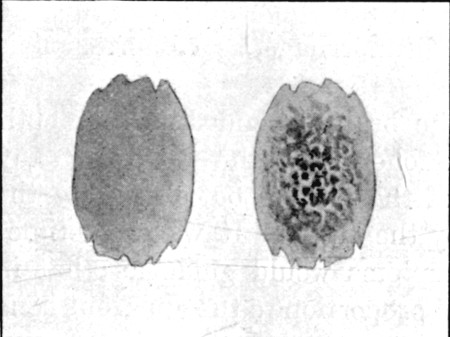

25a. Sections of Mauser Entry and Exit Wounds74